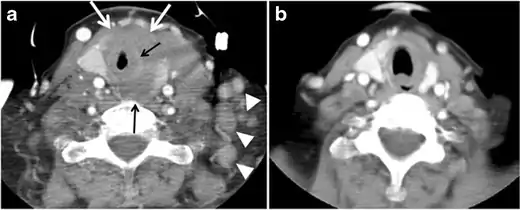

Fig. 5. A poorly differentiated invasive left thyroid mass in a 58-year-old female patient. a Sagittal greyscale neck ultrasound shows a large hypoechoic lesion with macro-calcification and micro-calcification. b Sagittal colour Doppler ultrasound shows left internal jugular vein filling defect with detected internal vascularity suggestive of tumour thrombus. c Enhanced axial and coronal CT scans of the neck show heterogeneously enhancing large lesion replacing the left thyroid lobe and extending to the isthmus and the medial aspect of the right thyroid lobe (white arrow). The mass and the conglomerate lymph nodes measure 12.5 × 7 × 5.8 cm (white arrows). d, e Axial enhanced CT scans show enlarged left cervical nodes (white arrow) and left internal jugular vein (IJV) thrombus (black arrows). Note the IJV distention and central enhancing portion in the upper cut (black arrow in e) concerning the tumour thrombus. f, g Enhanced axial CT scan of the upper chest demonstrate a mass extension into the retrosternal area, left tracheoesophageal groove, and posterior to the trachea (white arrows in f). There are multiple bilateral pulmonary nodules (white arrows in g).[1]

The radiologist must evaluate the central structures draping the thyroid gland including the trachea, oesophagus, larynx, and pharynx, as well as the recurrent laryngeal nerve. Invasion is suspected if the thyroid mass abuts the airway or oesophagus for more than 180 degrees. Luminal deformity, mucosal thickening and mucosal focal irregularity are more specific indicators of invasion. Obliteration of the fat planes of the tracheoesophageal groove in three axial images and signs of vocal cord paralysis are indicative of recurrent laryngeal nerve invasion. Invasion of these central structures meets the criteria for T4a disease (Figs. 5 and and6)6).[1]

Arterial invasion constitutes T4b disease, which may preclude curative surgery. More than 180 degrees of arterial encasement is suggestive of invasion, however, arterial deformity or narrowing is much more suspicious for invasion. The carotid artery is the most commonly involved artery; however, the mediastinal vessels should also be examined. Encasement of the carotid artery or mediastinal vessels for more than 270 degrees is unlikely to be resectable. On the other hand, occlusion or effacement of the internal jugular vein can occur without invasion and does not influence surgical resectability or staging. Asymmetry of the strap muscle and the tumour abutting its external surface are signs of an invasion. However, invasion of the pre-vertebral musculature is more challenging, as a large lesion can compress the muscle without invasion (Figs. 5 and and6)6).[1]

Finally, the possibility of metastatic disease should be excluded. PTCs and medullary thyroid carcinomas tend to metastasize to regional lymph nodes. According to the AJCC/UICC TNM staging system, the nodal stage is classified by site: N1a indicates level VI nodal involvement, including paratracheal nodes; N1b indicates unilateral or bilateral lateral cervical nodal disease or superior mediastinal nodal disease (Figs. 4, 55 and and6)6).[1]